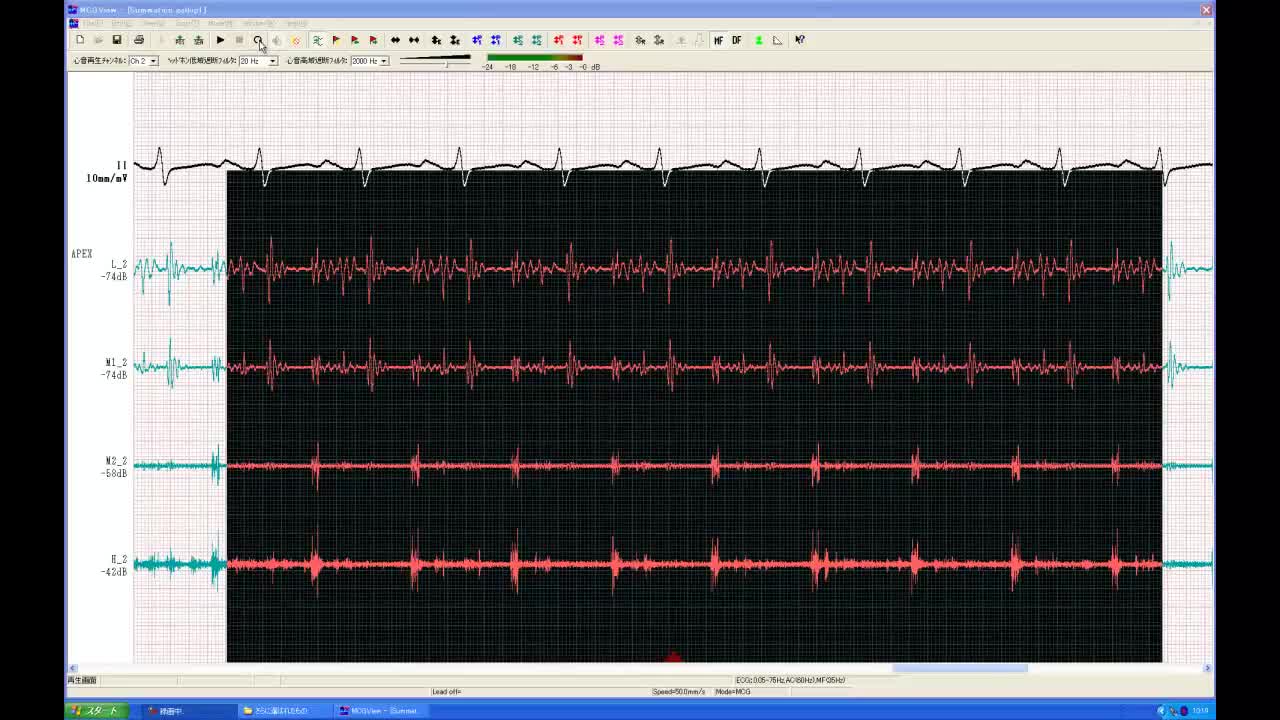

• 図7 summation gallop(重合奔馬調) a:胸骨左...

• 図7 summation gallop(重合奔馬調)a:心尖

• 図7 summation gallop(重合奔馬調) b